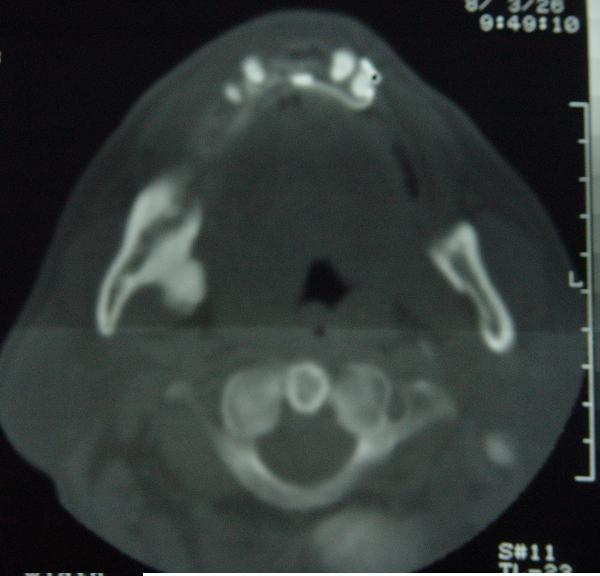

标题: CT12465:下颌骨肿瘤,请会诊 [打印本页]

标题: CT12465:下颌骨肿瘤,请会诊

发现下颌骨肿瘤近30年.逐渐增大.

考虑骨纤或骨化性纤维瘤。

考虑右侧下颌骨水平部及升部骨纤维异常增殖症可能性大。

考虑右侧下颌骨骨化性纤维瘤。